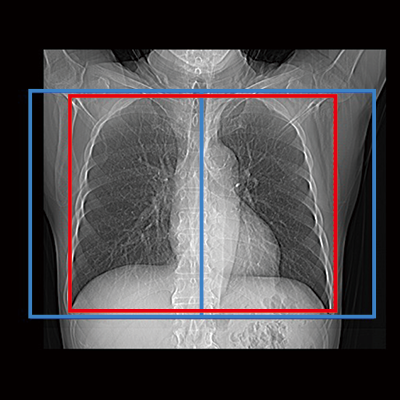

赤:自動設定された位置、青:自動設定された位置+マージン設定の位置

胸部